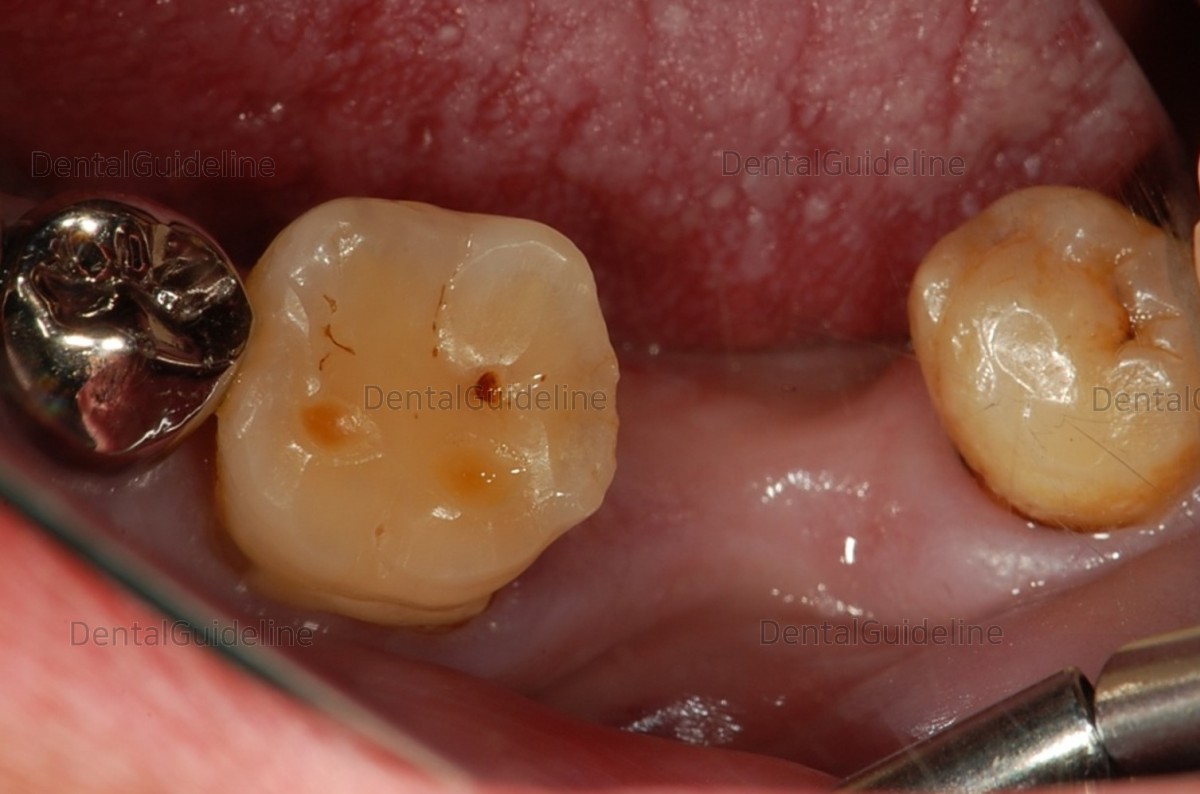

Pre-op intraoral view.